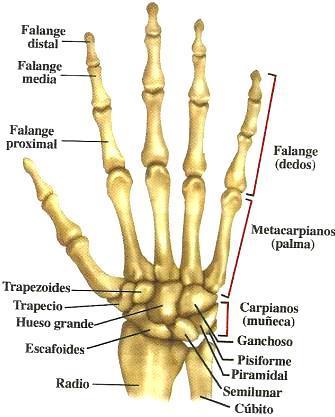

Figura 7. Anatomía ósea de la mano humana

La mano se constituye de 27 huesos, de los cuales 14 son falanges (3 falanges para los dedos índice, medio, anular y meñique, 2 falanges para el dedo pulgar); 5 huesos metacarpianos en la zona palmar, y 8 carpos en el área de la muñeca, se observa la distribución en la Figura 7 ( (Hernández Santos & Montoya Mejia, 2007)

Fuente Web: http://www.taringa.net/posts/info/19146128/10-cosas-que-no-sabias-sobrelas-manos.html